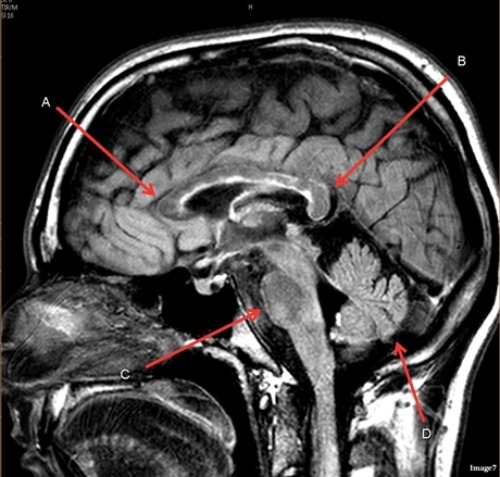

Letter D in Image 7 is pointing to:

A. Pons

B. Cerebellum

C. Hypothalamus

D. Genu of the corpus callosum

E. Splenium of the corpus callosum

Image 8 is an example of a ____ weighted sequence acquired in the ____ scan plane.

A. T1; Axial

B. T1; Sagittal

C. T2; Axial

D. T2; Sagittal

Letter A in Image 7 is pointing to:

Letter B in Image 7 is pointing to:

Letter C in Image 7 is pointing to:

Image 7 is an example of a _____ weighted sequence acquired in the ______ scan plane.

B. T2 FLAIR; Sagittal

Letter B in Image 8 is pointing to:

A. Tentorium

B. Corpus callosum

D. Fourth ventricle

E. Medulla oblongata

Letter E in Image 8 is pointing to:

C. Thalamus

Letter F in Image 8 is pointing to: